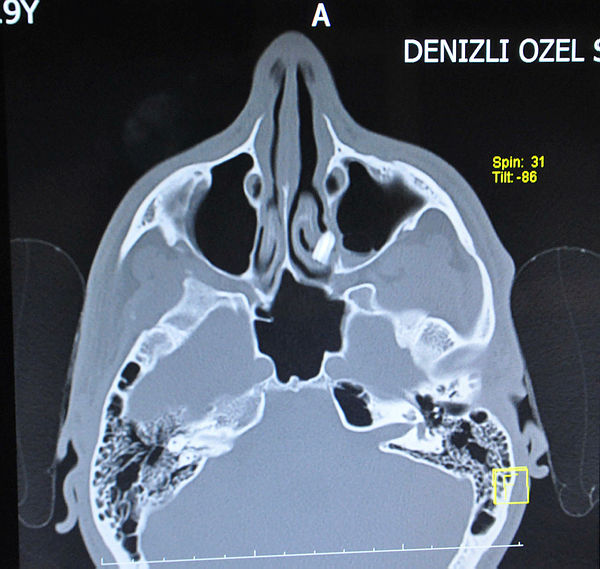

İyigün, hastanede görevli kulak, burun, boğaz uzmanı Opr. Dr. Ali Yüksel tarafından muayene edildi. Yapılan kontrolde, İyigün'ün burnunda, kemik eğriliği ve burun eti büyümesi tespit edildi ardından yüz tomografisi çekildi.

Tomografiyi kontrol eden Dr. Yüksel, İyigün'ün burnunun içinde yabancı cisim olduğunu gördü.

Dr. Ali Yüksel, hastası Utku İyigün'e burnunun içinde yabancı cisim olduğunu, ameliyatla çıkarılması gerektiğini söyledi. Perşembe günü Dr. Ali Yüksel tarafından ameliyata alınan İyigün'ün burnundan, yabancı cisim çıkarıldı. Tomografi incelemesinde, ilk olarak İyigün'ün çocukken burnuna kalem sokabileceği ve arka kapağının burun içinde kalıp, orta burun eti bölgesi sol gözünün yanına kadar ilerlemiş olabileceği düşünüldü. Ameliyatla çıkarılan cismin, yapılan son incelemede diş olduğu tespit edildi. Bunun üzerine İyigün, Dr. Yüksel'e 6 yıl önce bisiklet kullanırken, minibüse çarptığını, kazada yüzünden yaralandığını söyledi. İyigün'ün kazada çarpmanın etkisiyle diş kökünün yerinden aldığı darbe nedeniyle kopup, yüz boşluğu içine düştüğü, oradan da burun boşluğuna açılan doğal boşluktan geçerek, orta burun hizasına kadar ilerleyip, yerleştiği ihtimali üzerinde duruldu. İyigün'ün burnunda dişiyle 6 yıl yaşadığı ortaya çıktı.

Ameliyat hakkında bilgi veren Dr. Ali Yüksel, tomografide cismi önce kalem kapağı sandıklarını belirterek, "Ameliyatı yaptık, şikayetlerini giderdik ve yabancı cismi burnundan çıkardık. Cisim, sol orta burun eti içine gömülmüş şekildeydi. Cismi incelediğimizde diş kökü olduğu gördük. Hastamız, 6 yıl önce trafik kazası geçirmiş. Bize kaza anında diş köklerinin birinin kırılıp, yüz boşluğu içine düştüğünü söyledi..."

"...Enteresan olanı ise bu diş orada kalmamış, burun boşluğuna açılan doğal boşluktan içeri girip, orta burun hizasına kadar gelmiş ve buraya yerleşmiş. İlginç olan kısım bu. Literatüre de baktık, böyle vaka çok az. Hastamızın başına şansızlık sunucu olan gelen bir olay. Dişin orada 6 yıl boyunca kalıp, soluk borusuna ya da yemek borusuna kaçmayıp, enfeksiyon bile ortaya çıkarmamış olması önemli" dedi.

Burnunda dişiyle 6 yıl yaşayan Utku İyigün ise diş çıkınca çok şaşırdığını anlatarak, "Nefes alamama şikayetiyle hastaneye geldim. Doktor, bana çekilen tomografide, burnumun içinde yabancı cisim olduğunu söyleyip, gösterdi. Kalem kapağı olabileceğini sandık, ameliyatla çıkarıldı. Ameliyatın ardından cismin diş olduğunu öğrendim ve çok şaşırdım. Yaklaşık 6 yıl önce trafik kazası geçirdim, orada olabileceğini düşünüyoruz. Yüzüme darbe almıştım" diye konuştu.

İşte o diş...